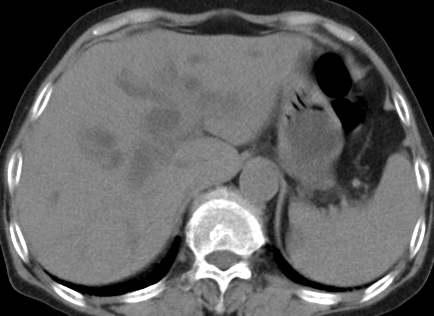

以下是引用齐原在2006-11-8 23:21:00的发言:[br]肝脏体积增大.肝表凸凹不平,肝内胆管扩张,胆总管扩张,胆总管末端突然截断,胰腺勾突增大,形态不规则.胰管扩张.考虑胰头癌.并低位梗阻性胆系扩张,胆囊炎.脾大.建议增强

以下是引用dyqct在2006-11-9 9:14:00的发言:[br]肝大,表面呈波浪状,肝内外胆管扩张,胆总管下端腔内见小结节状等密度影,胰管轻度扩张。胆囊显示不清。[br]考虑:1、胆总管下端占位性病变(等密度结石?壶腹部肿瘤?);[br] 2、肝硬化?[br] 3、建议增强扫描进一步检查。